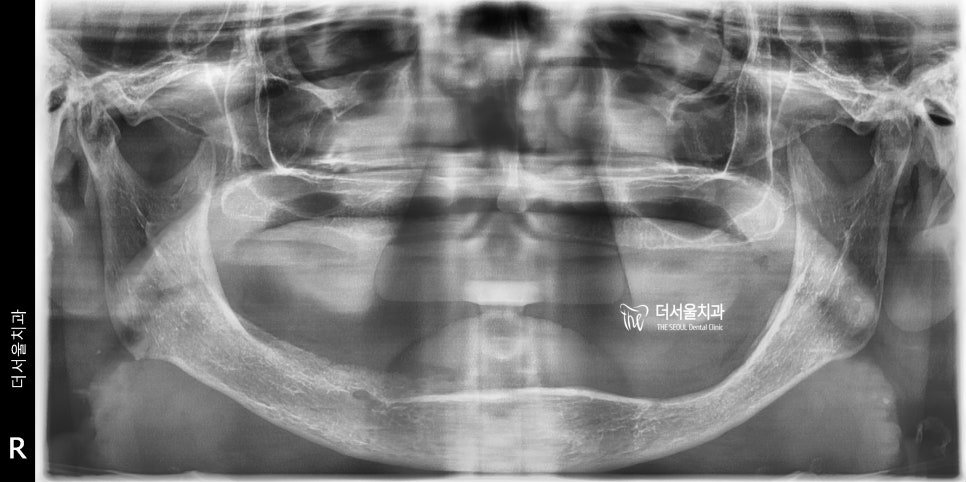

아래 엑스레이를 보면서 설명드릴게요.

파노라마 엑스레이인데, 이렇게 봤을 떄

중심선(mid line) 이 어디일까요?

그냥 가운데를 딱 찍으면 끝나나요?

아닙니다.

그렇게 되면 겉으로 봤을 때는

예뻐보여질 수 있겠으나 구강 내

기능이 올바로 형성 되지 않을 수 있습니다.

그래서 이럴 때는 구강 내 해부학적

구조물들을 통해서 중심선을 잡을 수

있는데 예를 들어서 incisive papilla 라는

절치유두나 설소대 등을 이용해서

가이드를 잡을 수 있습니다.

여기서 또 고려를 해야 될 것이 있습니다.

바로 수직고경 이라는

vertical demension 입니다.

환자마다 가지고 있는

수직고경의 값이 있는데

수직고경이라는 것은 어금니들끼리

서로 맞물렸을 때 만들어지는

코 끝과 턱 끝을 수평으로 이은 선들의

서로간의 거리입니다.

쉽게 말씀드리면,

턱관절(TMJ)가 편안히 있을 수

있는 위치라 보면 되겠습니다.

근데 무치악이면, 어금니도 없으니

수직고경의 값을 줄어들 수 밖에 없고

사진에서 보실 수 있다시피

아래 턱이 전방이동 되어있는 것을

볼 수 있습니다.

결국 안모의 변화도 일어나면서,

여러가지 부작용들을 초래하기 때문에

하루 빨리 치료를 받으셔야 되는

상황입니다.